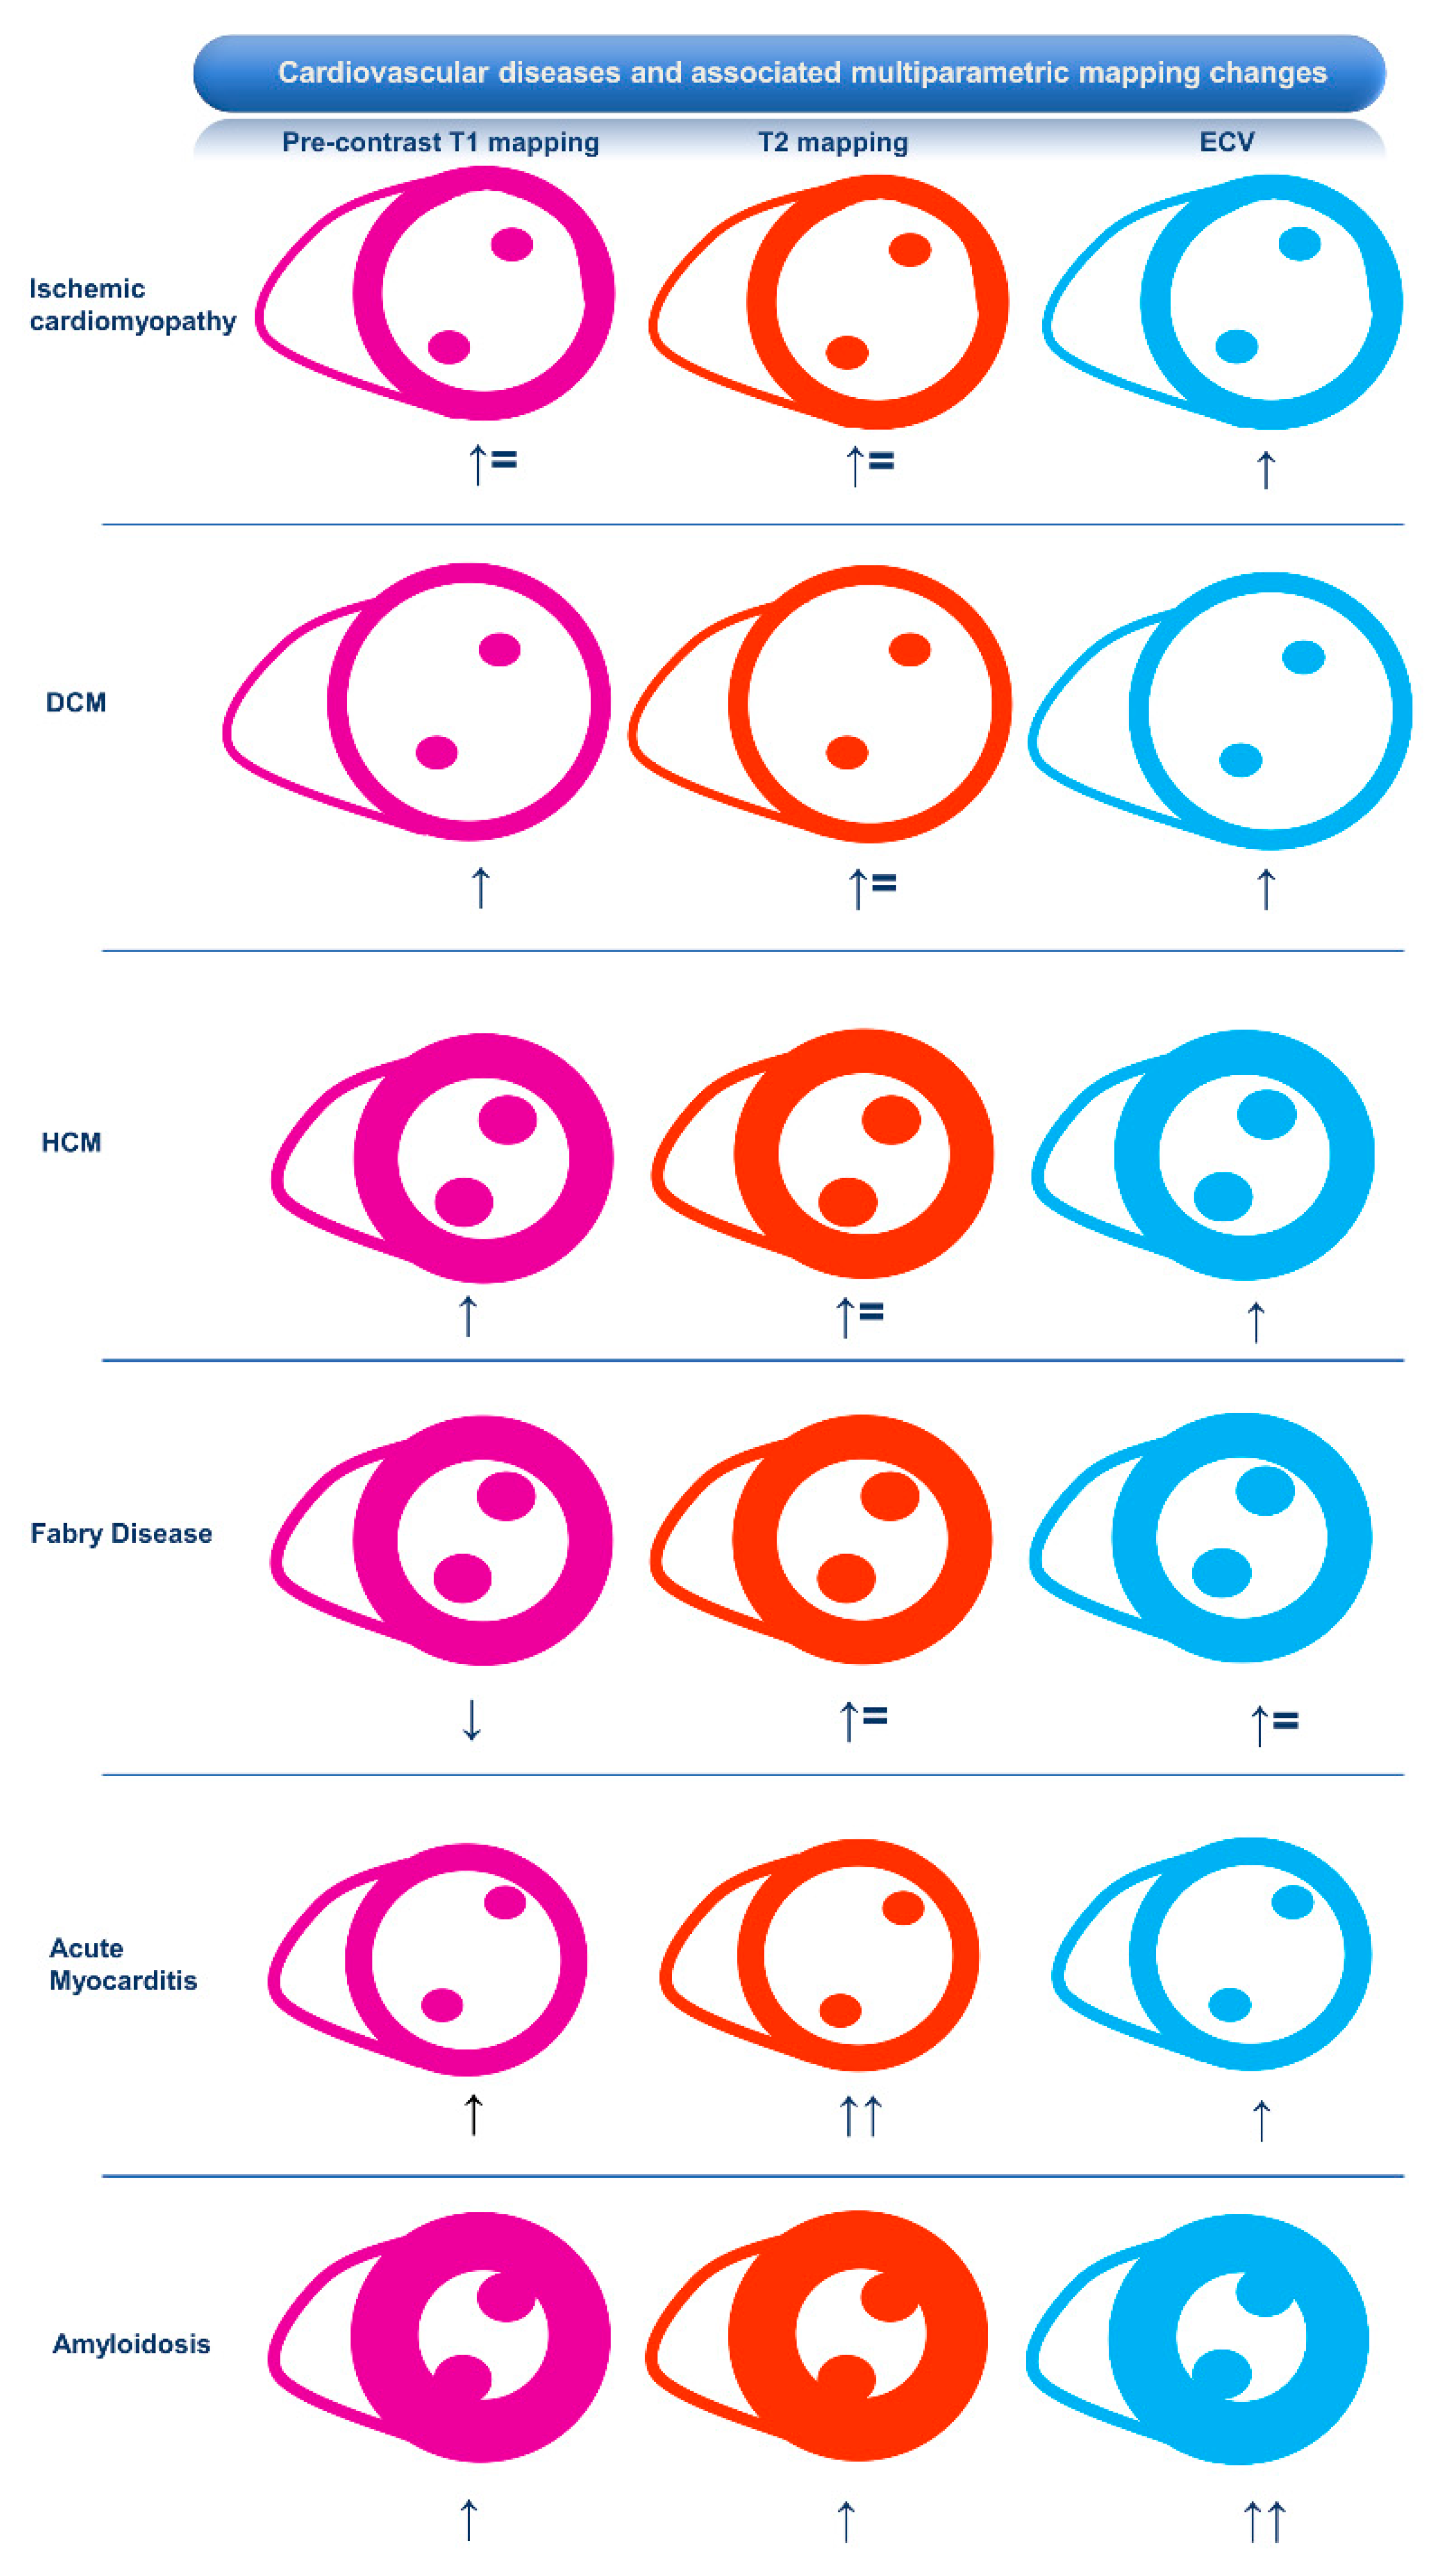

2. Association of CMR Mapping Alterations and Ventricular Arrhythmias in Cardiovascular Diseases

2.1. Ischemic Heart Disease

2.2. Inflammatory Cardiomyopathy

2.2.1. Myocarditis

2.2.2. Sarcoidosis

2.3. Hypertrophic Cardiomyopathy and Phenocopies

2.3.1. Hypertrophic Cardiomyopathy

2.3.2. Fabry Disease

2.3.3. Amyloidosis

2.4. Dilated Cardiomyopathy